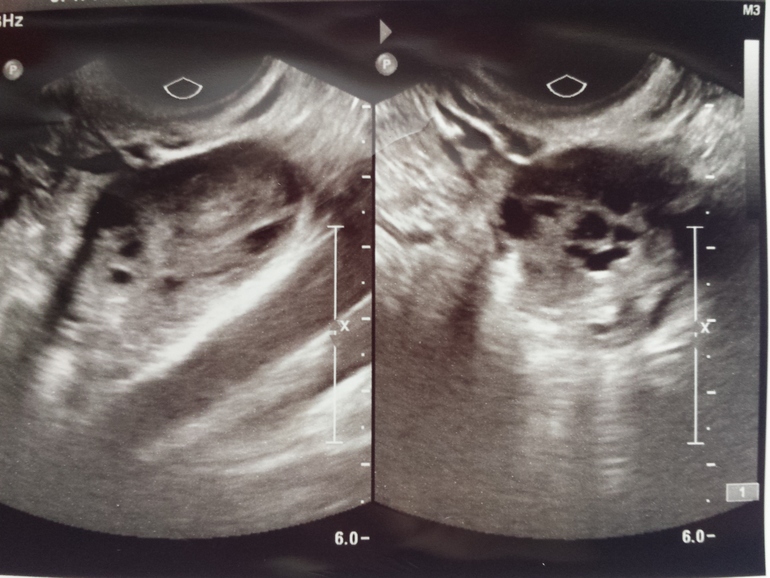

Привет девчонки ! Давно вас читаю, и тоже решила обратится за мнением! Я 10 октября была на узи и у гениколога. Это была середина цикла. Мне сказали (да и это видно по узи- фото ниже), что нет ЯК в правом Я, нету ж жидкости и фоликулы тоже маленькие. То есть она сказала что этот цикл без овуляции. Сегодня 2 ДЗ, сделала тест и там //? Как такое возможно или это тест бракованный?

На правом снимке, самое большое темное место, думаю здесь О была.